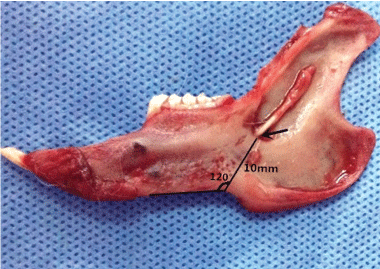

A total of 10 mandible specimens were obtained. The average side length of the mandibles was 70 mm (± 2 mm). In the mandibular ascending branch slightly biased to the root of the 5th molar, the mandibular foramen was observed as a funnel-shape, with the opening towards the upper rear. The vertical distance of the mandibular incisure and the mandibular foramen was approximately 10-11 mm. The angle between the anterior edge of the mandible and the connecting line of the incisure in the lower mandibular edge and the mandibular foramen was approximately 120° (Figure 2).

Figure 2: The positional relationship of the mandibular foramen (arrow) and the lower mandibular edge, as well as the incisure of the lower mandibular edge. View Figure 2